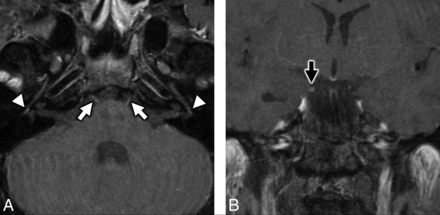

MRI of the brain in a patient with antecedent COVID-19 and new onset bifacial weakness and paresthesias subtype Guillain-Barré syndrome. Axial post-contrast T1-weighted SPoiled Gradient-Recalled (SPGR) MRI shows abnormal enhancement of the right oculomotor nerve (CNIII, white arrow, A), the cisternal segments of the abducens nerves (CNVI) bilaterally (white arrowheads, B), the distal canalicular segments of the facial nerves (CNVII) bilaterally (black arrows, C), and the proximal tympanic segments of the intratemporal facial nerves (CNVII) bilaterally (black arrowheads, C).